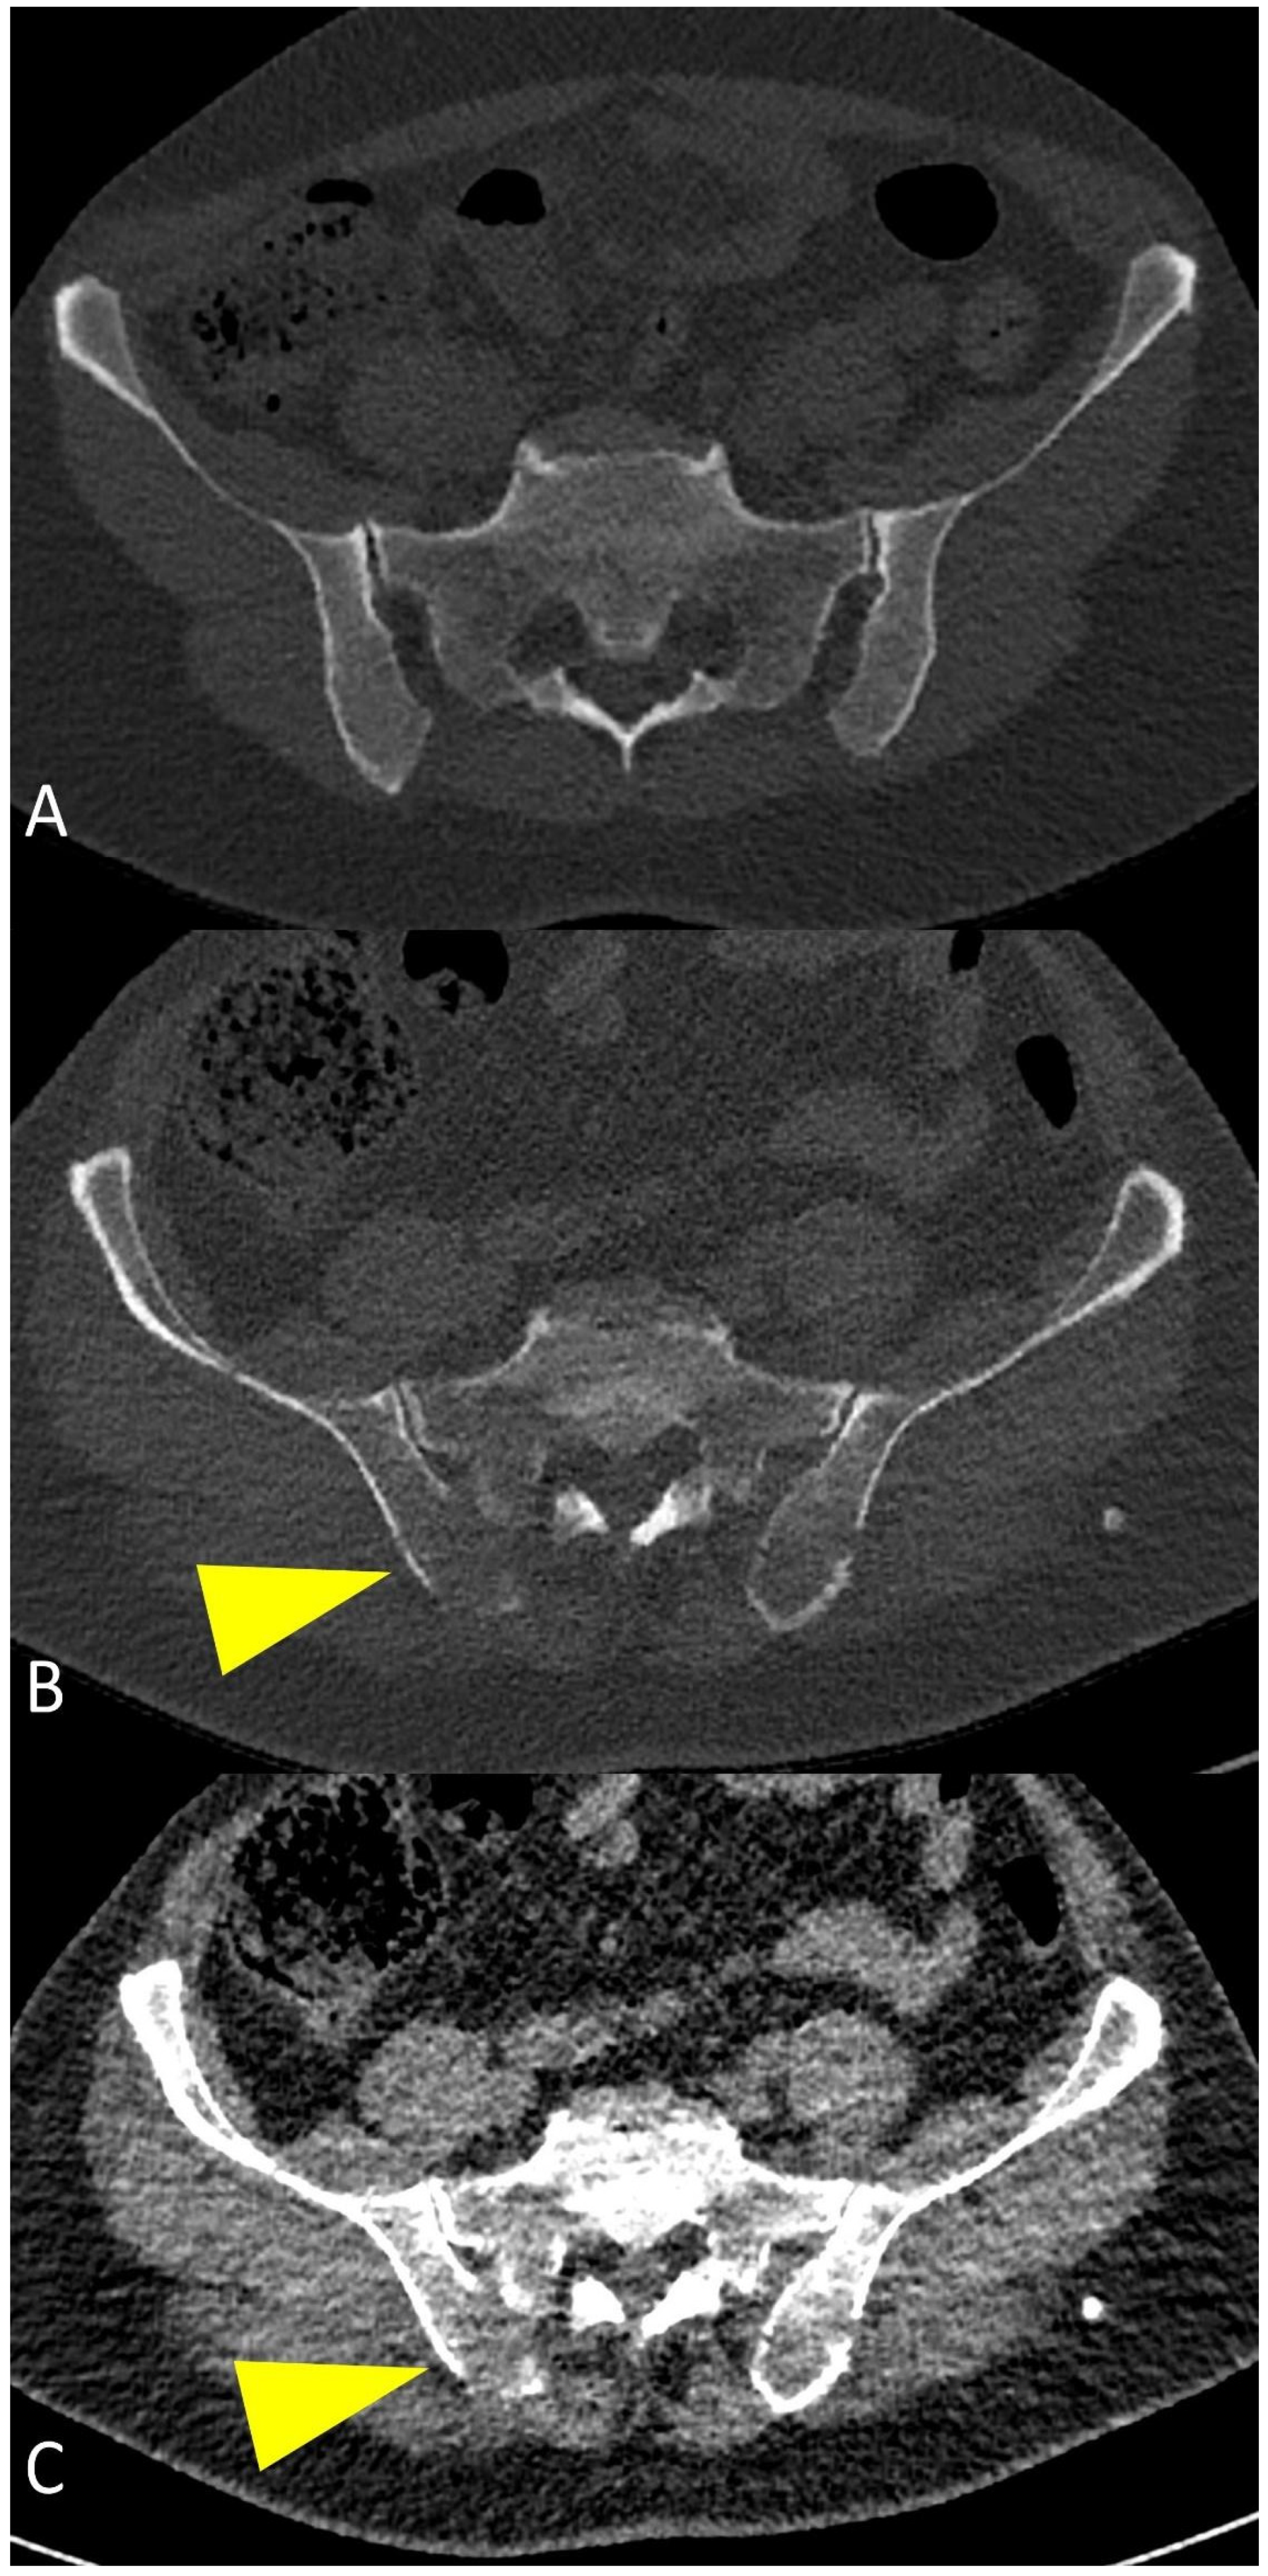

Figure 10.

(A) Axial CT images showing normal appearance of bone and bone marrow in an axial skeleton with dense trabeculae. (B,C) myeloma-related osteolysis appearing as focal destructive lesions of the trabecular bone with cortical interruption and without a sclerotic border (yellow arrowheads).

On the other side, WBLD-CT imaging is not so efficient in detecting early bone marrow infiltration, when the bone destruction is not such as to cause frank osteolysis, particularly in the dense trabecular bone of spine and pelvis, as it is not easy to determine whether myelomatous cellular infiltration replaces the fatty bone marrow component, due to the CT density of these sites being a function of bone marrow composition and trabecular bone mineralization (Figure 10); in this setting, in case of negative WBLD-CT, a whole-body or spine and pelvic MRI should always be suggested in the radiological report as it is the most suitable imaging technique for patients with smoldering or asymptomatic MM, to exclude myelomatous lesions, to confirm the diagnosis of smoldering MM, or to find undetectable-CT lesions [27].